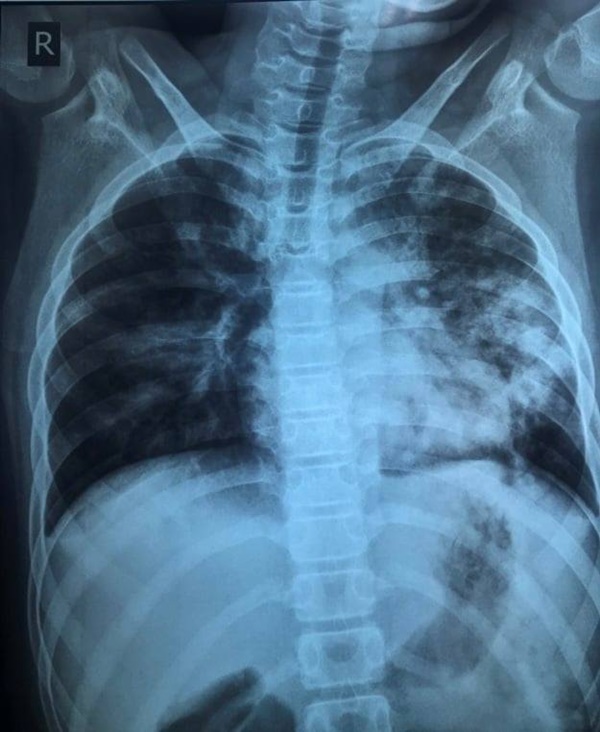

Hình ảnh X-quang phối của trẻ lúc nhập viện, tổn thương phổi nặng, dù triệu chứng rất kín đáo. Ảnh: BSCC.

Tại bệnh viện, nhịp thở của bệnh nhi 26-28 lần/phút, không quá nhanh so với tuổi. Tuy nhiên, chỉ số SpO2 của trẻ giảm xuống 92%, kết quả xét nghiệm PCR dương tính với nCoV. Kết quả chụp X-quang có tổn thương phổi nhiều, rối loạn đông máu.

Sau 5 ngày điều trị, tình trạng lâm sàng của trẻ cải thiện tốt, hết khó thở, giảm ho. Tuy nhiên, tổn thương phổi trên X-quang cải thiện chậm và vẫn còn giảm oxy máu khi thở khí trời từ 93-94%.

Sau 17 ngày điều trị và theo dõi sát triệu chứng và nồng độ oxy trong máu, bệnh nhi khỏi bệnh hoàn toàn, tổn thương phổi trên X-quang cải thiện đáng kể. Bệnh nhi cũng có kết quả xét nghiệm PCR âm tính. Hiện, trẻ đã được xuất viện.